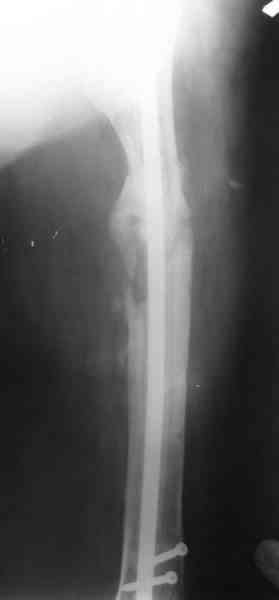

В настоящее время наш пациент ( см. http://weborto.net/forum/1177351385/) ходит с одним костылем. У него периодически открывается свищ на задне-наружной поверхности бедра с умеренным серозно-гнойным отделяемым. Температура тела и анализы нормальные. На рентгенограммах имеются признаки консолидации ложного сустава.

Иллюстрации:

1, 2, 3, 4 - рентгенограммы бедра от 8 августа этого года (через четыре месяца после операции);